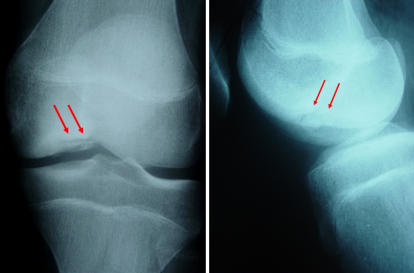

Osteokondritis dissekans tanısı için ortopedi doktorunuzun yapacağı ayrıntılı bir diz muayenesi sonrası röntgen grafileri hastaların çoğunda yeterlidir (Resim 1). Bilgisayarlı tomografi (BT) ve Manyetik Rezonans Görüntüleme (MRG) gibi ileri görüntüleme yöntemleri hastalığın evresinin belirlenmesi, tedavi planının yapılması ve tedavi sonucunun değerlendirilmesi için gereklidir (Resim 2). Artroskopik değerlendirme, evreleme ve tedavi planı için en önemli araçtır. Bir kamera kullanılarak eklem içi incelenir, parçanın boyutları, yerleşimi, altındaki yatağa olan bağlantısı ve vida tespitine uygun olup olmadığı nihai olarak artroskopi sırasında değerlendirilir ve tedavi aşamasına geçilir.